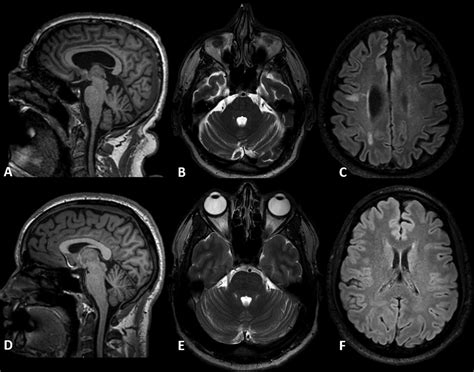

• Imaging Studies: Such as MRI or CT scans to visualize the nerves and rule out other causes of symptoms.